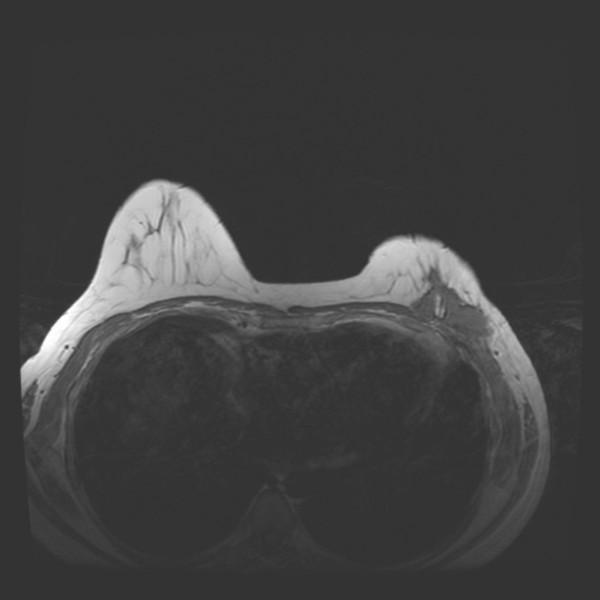

CASE PRESENTATION

We report a patient with three post-surgical recurrences of fibromatosis of the breast over a seven year period. The fibromatosis was found to be involving the chest wall musculature and causing persistent and worsening pain. An aggressive operative strategy was undertaken, consisting of mastectomy with en bloc resection of the underlying chest wall musculature, ribs, and parietal pleura.

病例报告

我们报告一名患者,在七年时间里乳腺纤维瘤病术后复发三次。发现纤维瘤病累及胸壁肌肉组织并导致持续且加重的疼痛。采取了积极的手术策略,包括乳房切除术并整块切除下方的胸壁肌肉组织、肋骨和壁层胸膜。